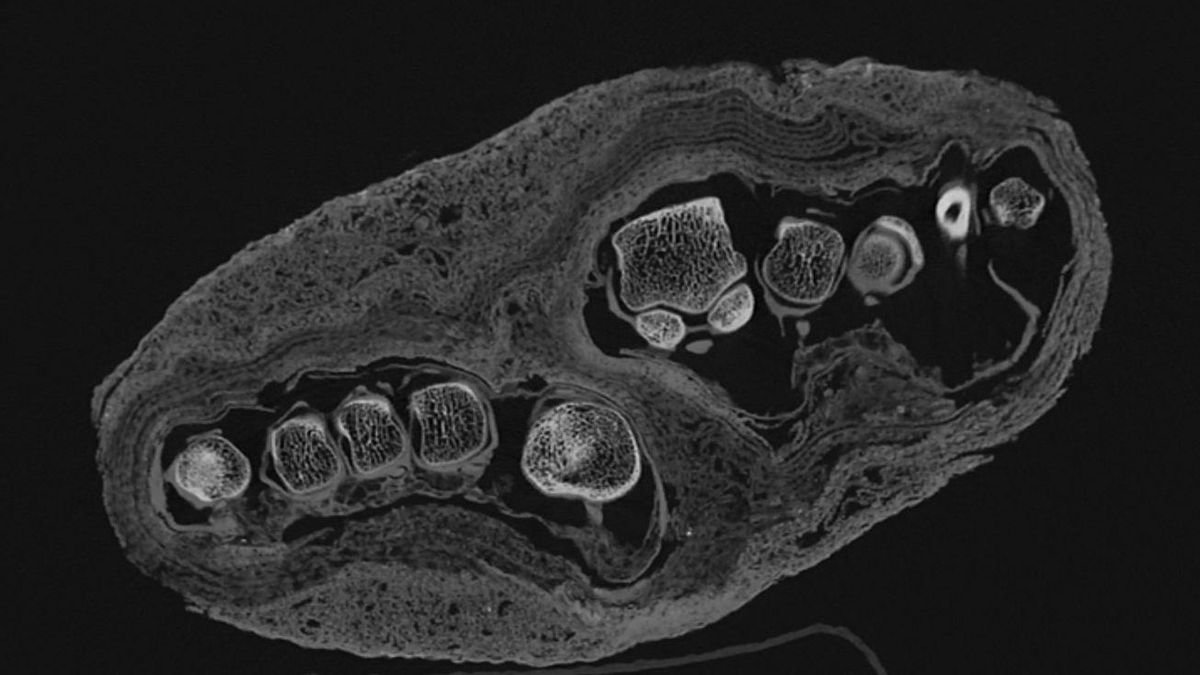

Esta nueva generación de escáneres permite visualizar con gran precisión estructuras internas complejas, como huesos, dientes y hasta las capas de vendaje utilizadas para la momificación. Este avance no solo facilita una mejor estimación de la edad de los individuos, sino que también sienta las bases para hacer futuras reconstrucciones en 3D de las momias.

Análisis de huesos de las momias del antiguo Egipto.

Actualmente, los investigadores siguen analizando una mano momificada con el objetivo de determinar si esta corresponde a un menor o a un adulto, para lo que evalúan no solo el tamaño y el desarrollo sino también las características morfológicas de los huesos. Además de la edad, podrían estimar el sexo del individio al que perteneció esta parte del cuerpo.